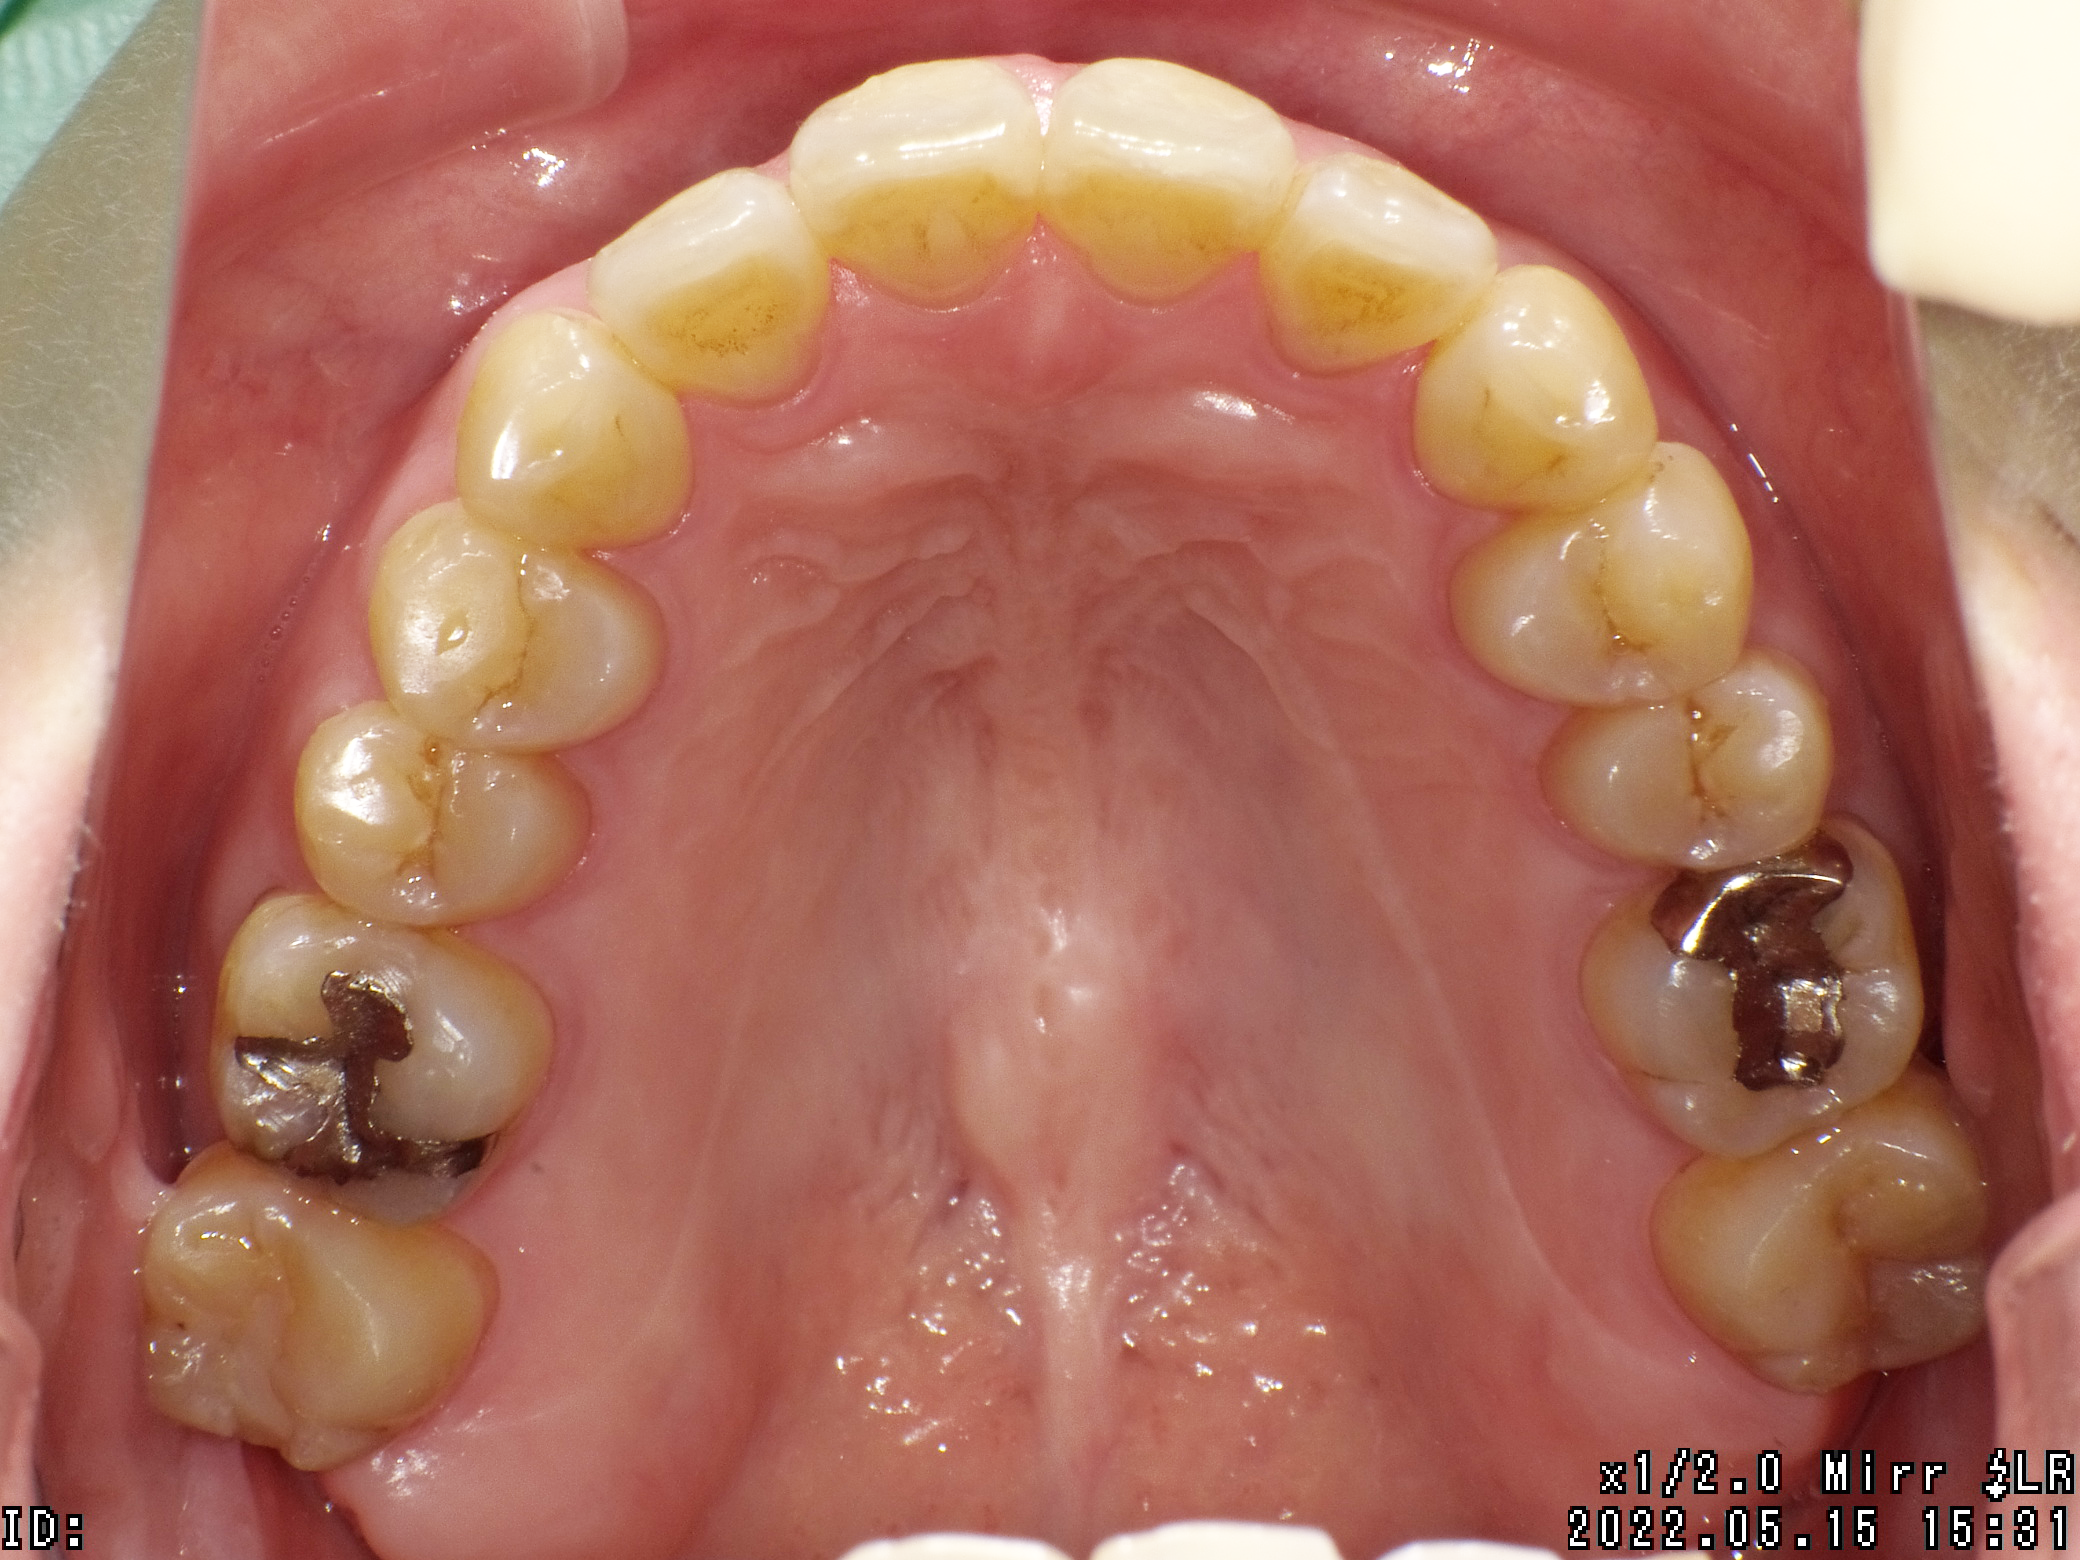

| 治療期間 | 2021年6月13日 〜2022年12月11日 |

|---|---|

| 治療費用 | 約770,000円 |

| 抜歯有無 | 抜歯あり |

| 矯正箇所 | クリアブラケット矯正 |